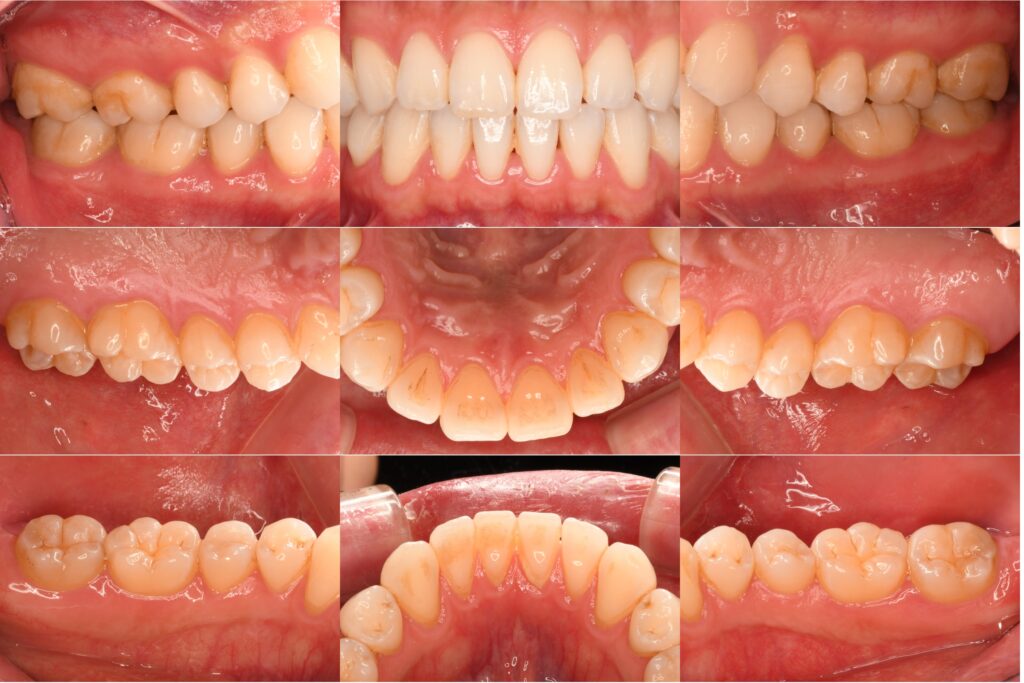

左下2・3・4番の虫歯を即日CRで治療しました【保険診療】

「虫歯を治したい」という主訴でご来院されました。診査の結果、左下2・3・4番に虫歯が確認できたため、即日でコンポジット…